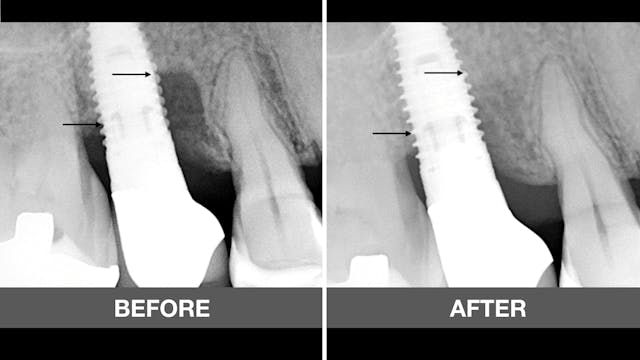

In this dental video by Dr Jovanovic a meticulous procedure involving the uncovering of two anterior implants with a mucogingival technique employing a roll flap and a vestibuloplasty with a gingival strip graft sourced from the palate. Through step-by-step demonstrations, the video showcases the precision and expertise required for successful implant uncovering and soft tissue management.

Furthermore, the video highlights the integration of cutting-edge digital technology in dental practice by illustrating the immediate temporization phase. Oral scanning and 3D printing are utilized to create custom temporaries, ensuring optimal fit and aesthetics for the patient during the crucial soft tissue healing period.